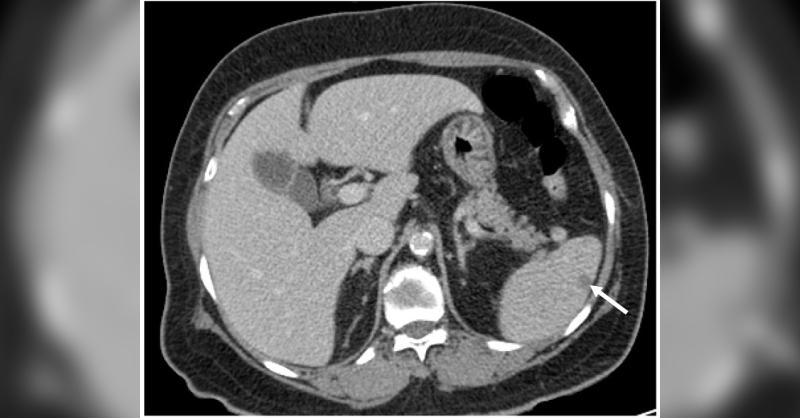

A Rare Case of Microscopic Polyangiitis Presented with Splenic Infarction

A 74-year-old woman presented at the hospital having numbness in both of her hands and weakness in her left arm. She had previously experienced a cerebral infarction and was currently on oral medications for hypertension and dyslipidemia. The right basal ganglia had an acute focal infarction, according to MRI. A subpleural nodule in the right lower